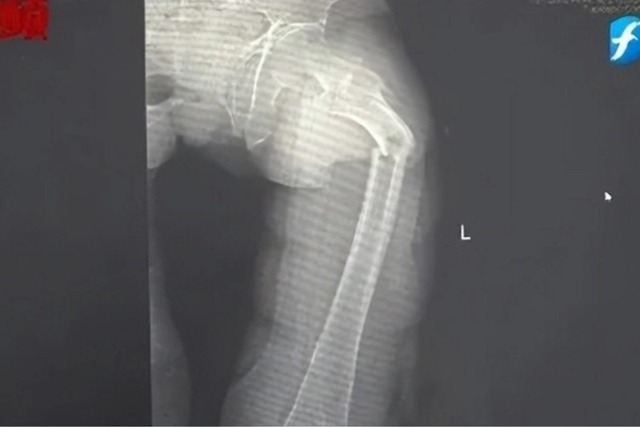

Đến nửa đêm, anh Cung bị giật mình tỉnh giấc vì cơn đau ở đ:ùi. Anh phát hiện ra mình không thể đi lại được nhưng cố chờ đến trời sáng hẳn rồi nhờ người nhà đưa đi bệnh viện. Kết quả chụp X-quang tại Bệnh viện Nhân dân số 2 Phúc Kiến (Trung Quốc) khiến anh Cung sốc nặng: x:ương đ:ùi trái của anh bị gãy làm hai mảnh.

Bác sĩ Đông Trung, Trưởng khoa Chấn thương và Chỉnh hình của bệnh viện cho biết anh Cung bị gãy x:ương bệnh lý, xảy ra do loãng x:ương sớm rất nghiêm trọng. Dù mới 35 tuổi nhưng x:ương của anh Cung được bác sĩ nói vui là "xốp như tổ ong", khối lượng x:ương tương đương với một cụ già 80 tuổi.

Hình ảnh x:ương đ:ùi bị gãy đôi vì loãng x:ương sớm của anh Cung